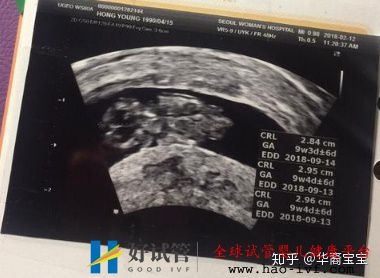

最烦的阶段是打促排针,能打上十二天,每天一针,然后最怕又没任何感觉的是取卵和移植,有麻醉无痛感,,,最后最让人抓狂的是等待怀孕的移植后十几天里,心情宛如热锅蚂蚁。当然我是怀上了的,不然也不会跟你们分享啦!一次怀上,已验胎心,男孩子,目前14+2周。

(胎芽胎心)